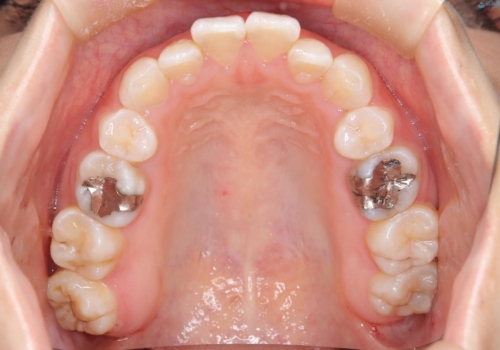

- 子供のころに矯正治療をされていたが、後戻りをしてしまったという20代女性の患者様です。上顎左右の2番が、咬合時に下顎の歯よりも内側に入っているクロスバイトという状態でした。奥歯の咬合関係は変えずに、マウスピース矯正にて前歯の並びを綺麗なアーチに仕上げました。再度後戻りしてしまうリスクを軽減させるために、リテーナー(保定装置)をお渡ししています。